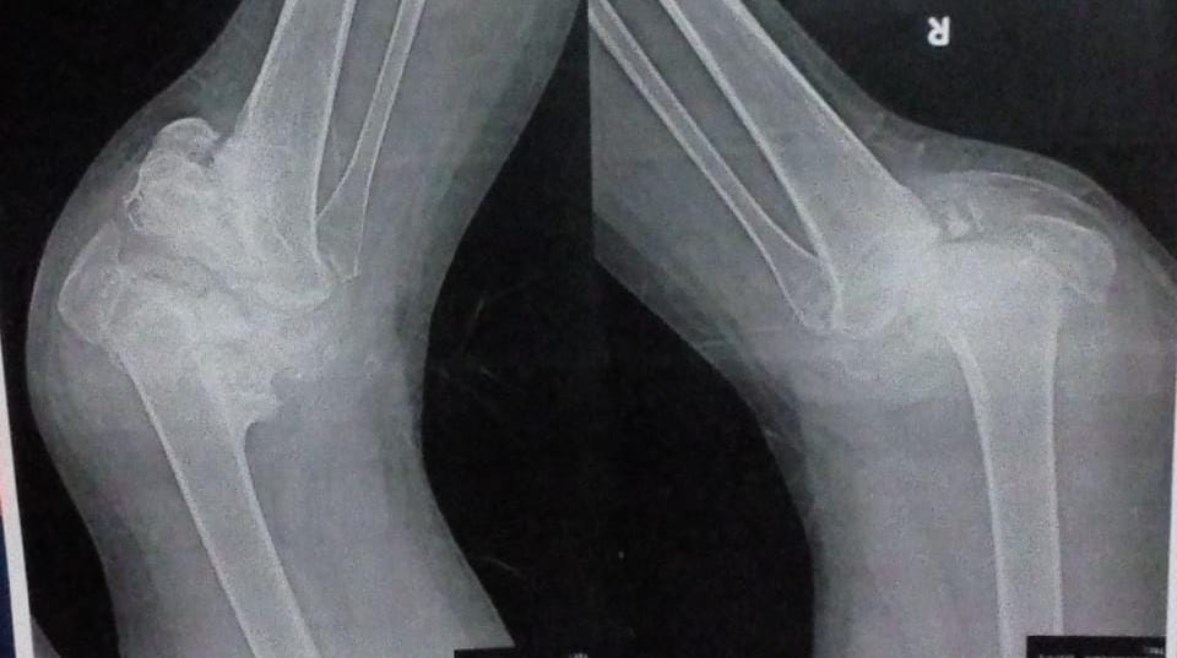

أشعة على ركبتي دعاء توضح التآكل

الفتاة تعايشت مع السكري من النوع الأول منذ كانت في الصف الأول الابتدائي، ولم تكن تعلم أن القدر يخبئ لها اختبارًا أصعب، وهو إصابتها بمرض “شاركوت” (اضطراب عصبي نادر) أدى إلى تلف أعصابها، وتفتت كامل لعظام مفصلي ركبتيها وتآكلهما.

أتضح للأطباء أن الركبة تآكلت بنسبة كبيرة، وتحتاج إلى توافر إمكانيات تقنية حديثة لتركيب ركبة تعويضية بمواصفات دقيقة لا توجد في مصر، بالإضافة إلى ارتفاع نسبة المخاطر في حال إجراء الجراحة محليًا، ما قد يؤدي إلى العجز الكامل أو البتر.

تستغيث دعاء عبر “تليجراف مصر” وتطالب الجهات المعنية بتبني حالتها وتوفير نفقات العلاج، موضحة أن التآكل زحف إلى ركبتها اليمنى خلال السنوات الثلاث التي قضتها حبيسة بيتها، وأنها لن تقدر على دفع تكاليف العلاج والسفر إلى الخارج، التي تقدر بنحو 2 مليون جنيه.